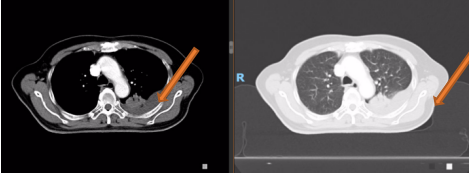

胸部平扫+增强CT(2020-08-27):食道中段管壁增厚,上下累及约4.5厘米(约胸5/6椎间隙水平至胸8椎体上缘水平),增强后可见轻度强化,隆突下见境界不清淋巴结。左肺上叶尖后段及相邻左肺下叶背段交界处见团块状直径约2.5厘米软组织密度灶,边缘可见毛刺,左侧胸腔积液,左下肺膨胀不全。右肺下叶见少许条状影。结论:1、食管癌。2、左肺上叶尖后段病灶,符合肺癌。左侧胸腔积液,左下肺膨胀不全。

病理结果:(肺占位组织)见癌组织浸润,结合免疫组化结果,病变为肺浸润性腺癌。免疫组化:CK7(+)、TTF-1(+)、NapsinA(+)、Syn(-)、P63(个别细胞+)、P40(-)。

肺癌组织NGS结果:1、MET基因c.3028+1G>T第14外显子跳读突变,组织丰度:7.5%,FDA批准药物:克唑替尼、卡马替尼、特泊替尼等靶向治疗。2、未检测到MSI-H。3、未检测到ALK、BRAF、BRCA、EGFR等突变。

同时性食管、肺双原发癌(食管鳞状细胞癌cT3N0M0 IIb期;左肺腺癌cT3N0M0IIb期,MET基因跳跃突变阳性)